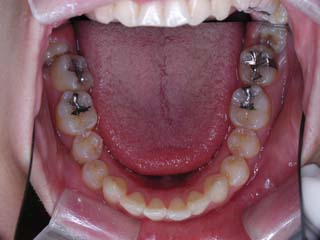

使用した主な装置名:TPB、マルチブラケット装置、歯科矯正用アンカースクリュー

抜歯/非抜歯および抜歯部位:抜歯(上顎左右第一小臼歯)

治療期間:動的処置2年6か月、経過観察3年